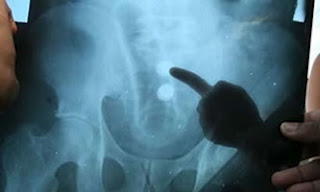

Um procedimento cirúrgico curioso deixou médicos e enfermeiros surpresos na manhã de ontem, em Manaus. Um homem de 42 anos, cujo nome não foi divulgado, deu entrada no Hospital e Pronto Socorro Platão Araújo, na Zona Leste da cidade, com um vibrador de 22 centímetros introduzido no ânus.

O objeto foi retirado por meio de procedimento cirúrgico que durou pouco mais de uma hora. A unidade médica ainda informou que esse tipo de cirurgia é delicado e tem duração aproximada de uma hora para ser finalizada.

O Boletim Médico do Platão Araújo, informava que havia necessidade de retirar o ‘objeto estranho’ na via retal do paciente com urgência.